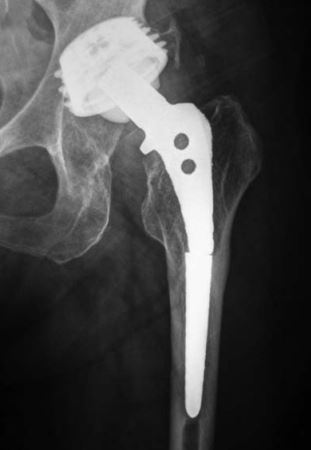

我的人工全髋关节置换翻修手术需要做大粗隆延